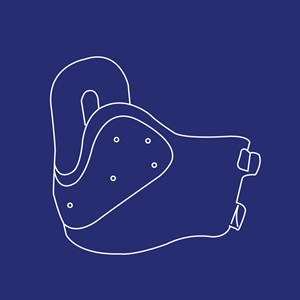

Halskraver

Type: pdf

Størrelse: 1003 KB